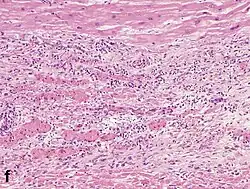

Micrograph of a myocardial infarction (ca. 400x H&E stain ) with prominent contraction band necrosis.

Under the microscope, myocardial infarction presents as a circumscribed area of ischemic, coagulative necrosis (cell death). On gross examination, the infarct is not identifiable within the first 12 hours.[22]

Although earlier changes can be discerned using electron microscopy, one of the earliest changes under a normal microscope are so-called wavy fibers.[23] Subsequently, the myocyte cytoplasm becomes more eosinophilic (pink) and the cells lose their transversal striations, with typical changes and eventually loss of the cell nucleus.[24] The interstitium at the margin of the infarcted area is initially infiltrated with neutrophils, then with lymphocytes and macrophages, who phagocytose ("eat") the myocyte debris. The necrotic area is surrounded and progressively invaded by granulation tissue, which will replace the infarct with a fibrous (collagenous) scar (which are typical steps in wound healing). The interstitial space (the space between cells outside of blood vessels) may be infiltrated with red blood cells.[22]

These features can be recognized in cases where the perfusion was not restored; reperfused infarcts can have other hallmarks, such as contraction band necrosis.[25]